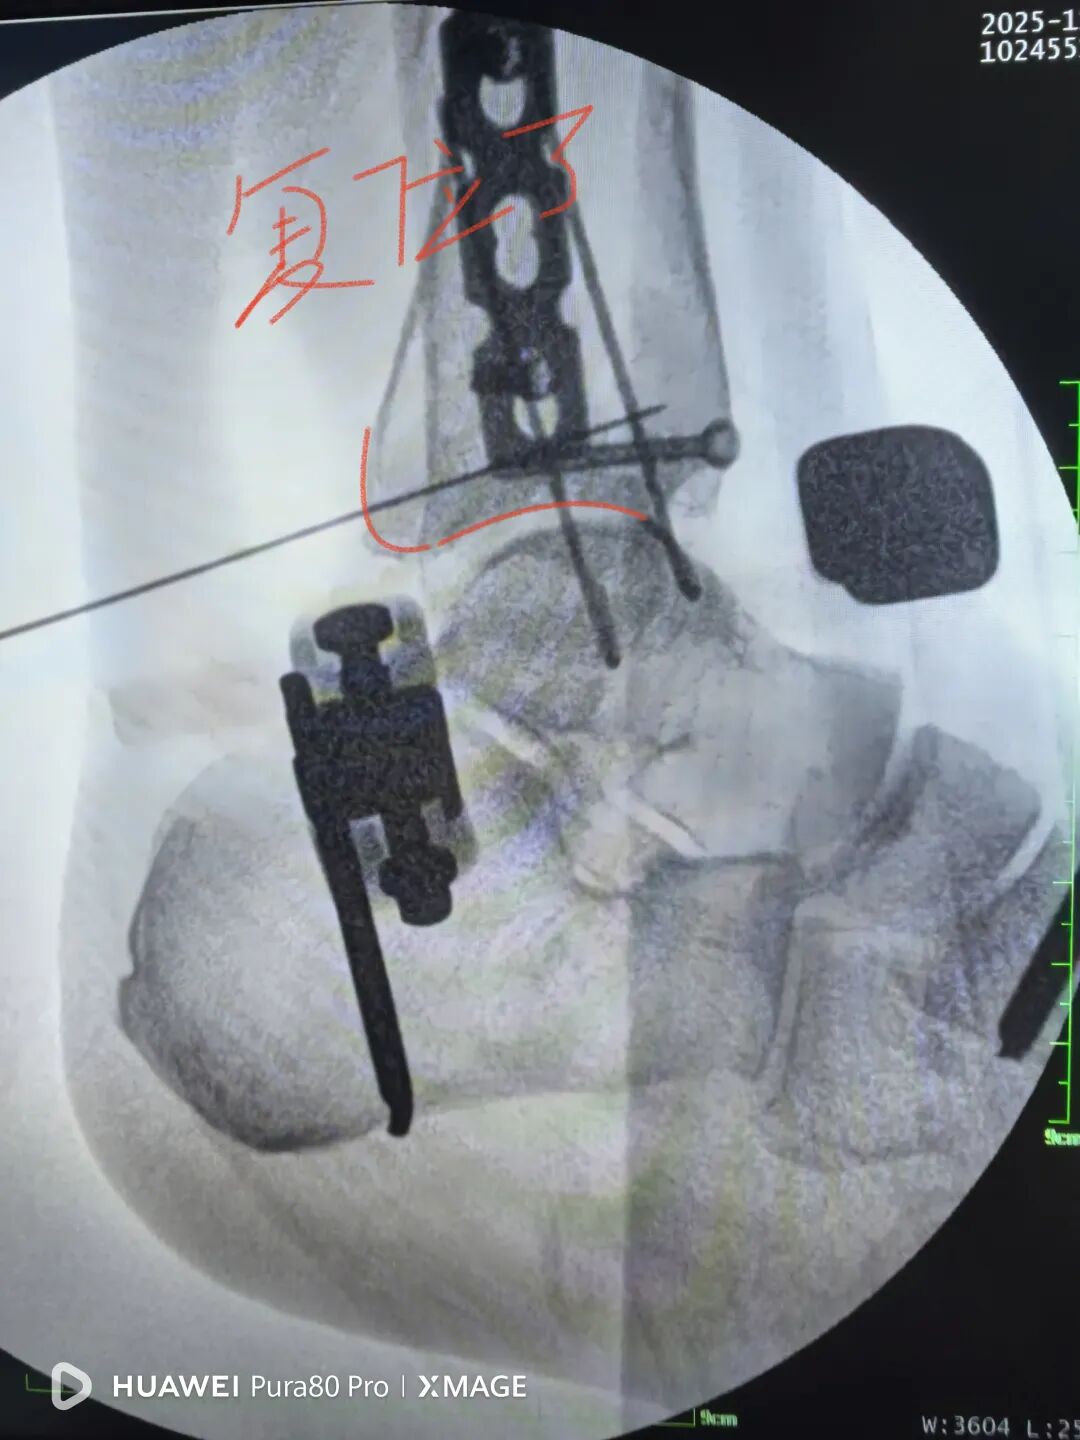

没有松外架

骨折没复位